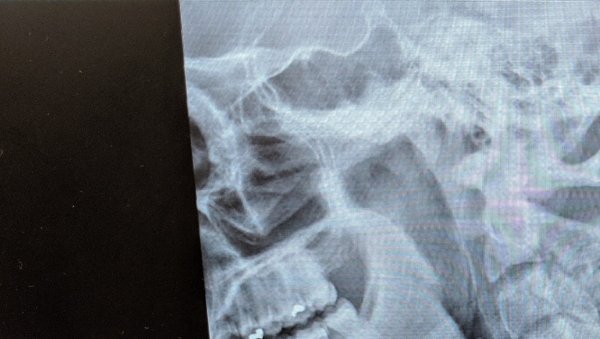

xray

This X-Ray shows the location of Matthew Ewell's spinal injury.

"I landed, dying almost instantly from impact, and crushed my C7 vertebrae, causing paralysis," he told a crowd recently at an Old Dominion University gathering. "I had to be resuscitated twice, flatlining for roughly seven minutes."

Ewell was initially diagnosed with an unrecoverable incomplete spinal cord injury. He was paralyzed from the chest down. His plans for a career in the military would vanish, and his life would change forever.